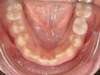

Cas N°6 : Description

Correction majeure des deux arcades dentaires liée à une mandibule rétrusive

Avant

Après